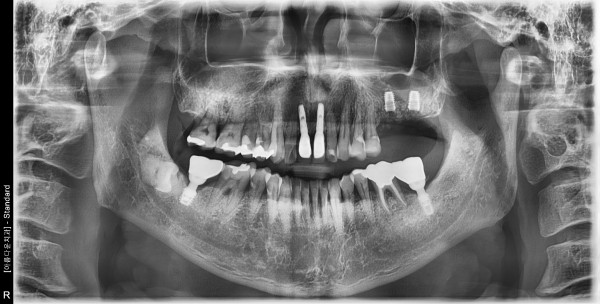

50대 남성 임플란트 식립

8a08f77c64fcbf7fd4a8101c03ab8c69_1760922